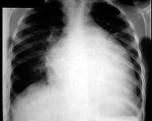

问题 男,24岁,反复胸闷气短4年,近1周加重,端坐时即感胸闷,伴咳嗽、下肢水肿,肝脏肿大。超声心动图示心脏扩大,室壁变薄,EF值20%,二尖瓣、三尖瓣中度反流。胸片如图所示。 若经治疗,患者病情好转稳定,需小剂量开始加用 ( )

选项 A、地高辛 B、消心痛(异山梨酯) C、卡托普利 D、双氢克尿塞 E、倍他乐克(美托洛尔)

答案 E